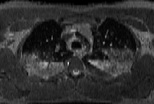

Visible Human male: Sectio transversalis 1361

CT

NMR

Pd T1 T2